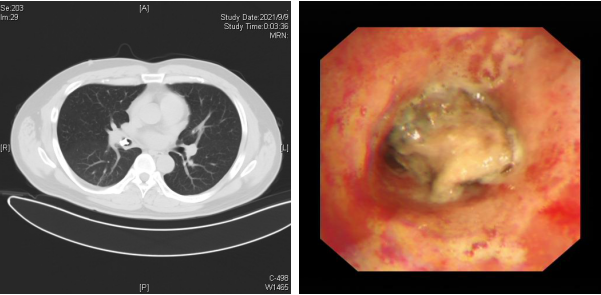

近日,34岁的李先生在吃饭时不小心将食物吸到了气管里,随后出现持续性剧烈干咳,少量咯血,呼吸时气短,并能听到胸腔内的哮鸣音。李先生赶紧来到清华大学附属北京清华长庚医院急诊科就诊,胸部CT检查显示右主支气管内高密度异物影。急诊医师立刻联系呼吸与危重症医学科紧急会诊,主治医师赵景全看到李先生的影像后,考虑气道异物较大,立刻为患者联系安排紧急气管镜检查,探查可见患者右中间段支气管内有一灰褐色异物,呈现不规则形态,几乎完全阻塞了支气管管腔,与支气管嵌顿紧密,远端气道无法窥及。

患者肺部CT影像及气管镜下的异物